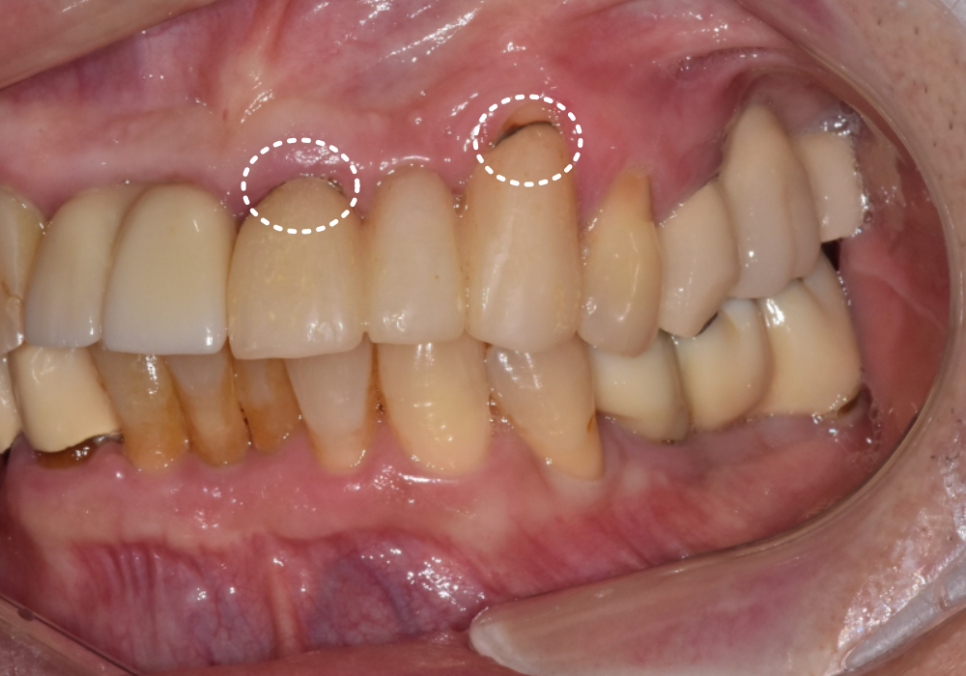

입안 상태를 조금 더 꼼꼼히 들여다보니,

송곳니(#23)는 잇몸이 내려가

뿌리 쪽에 충치가 보였고,

앞니(#21)는 보철물 안쪽이

거뭇거뭇하게 비쳐 보이는 게

직감적으로

'아, 속에서 꽤 큰 문제가 생겼구나' 싶었어요.

특히 잇몸이 많이 내려간 송곳니(#23)의 경우,

230315

무너진 라인을 무시하고 보철물만 씌우면

치아가 비정상적으로 길어 보여

자칫 인상이 부자연스러워 보일 수 있어요.